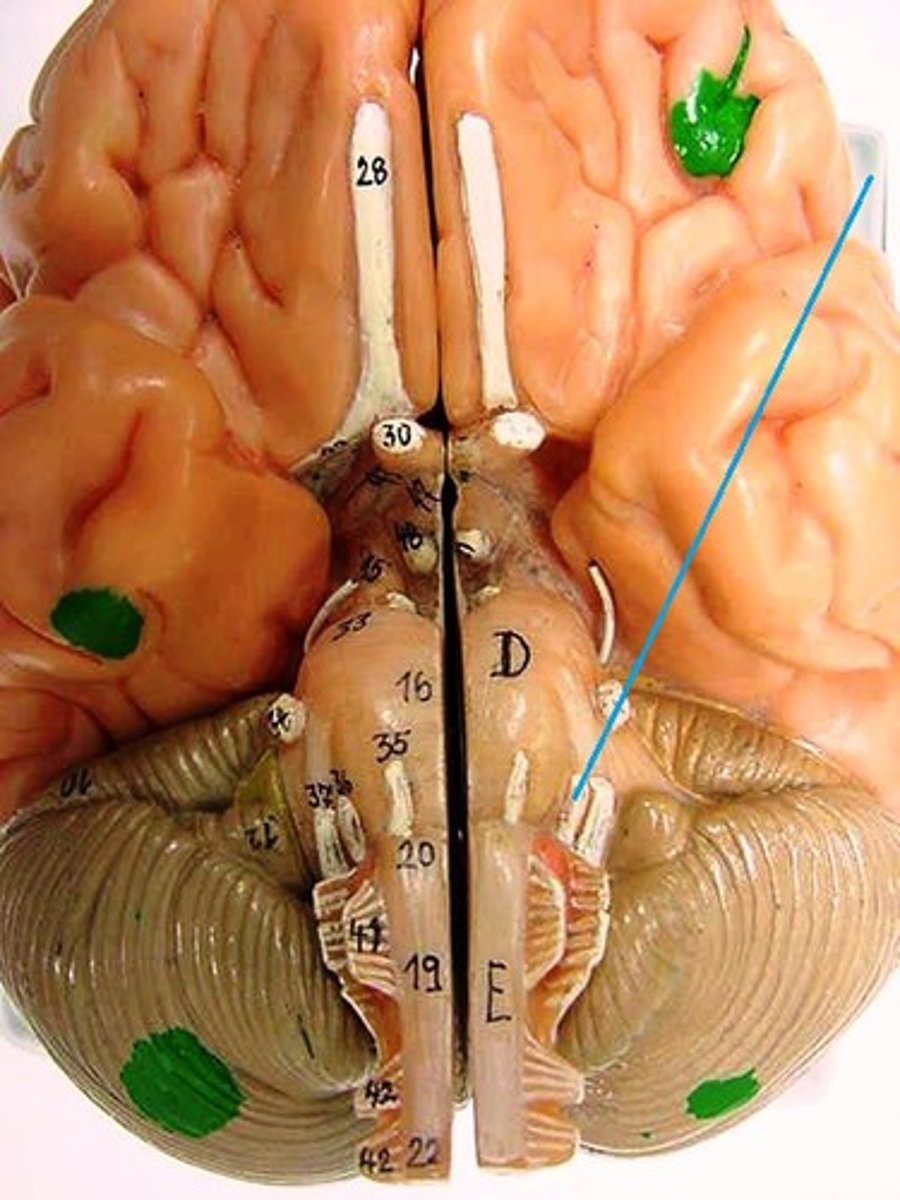

optic chiasm

optic nerve

optic tract

Primary visual cortex

Primary auditory cortex